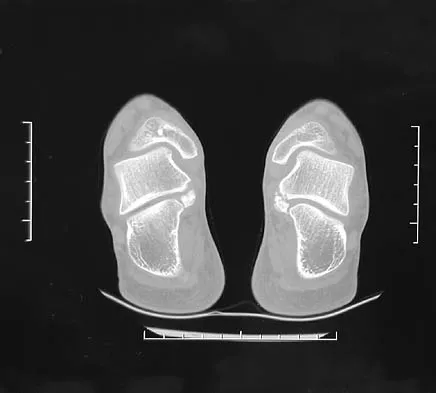

Figure 8 shows the CT scan of an 11-year-old boy who has had a 1-year history of worsening painful flatfeet. He reports pain associated with physical education at school, especially with running and jumping. Management consisting of activity restriction, anti-inflammatory drugs, and casting has failed to provide relief. Treatment should now consist of

Explanation